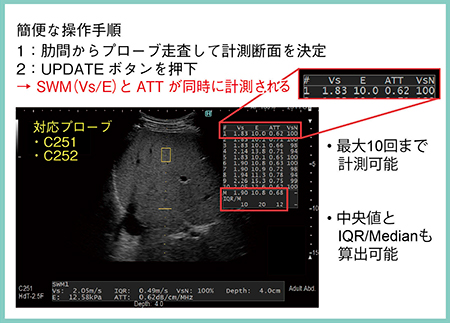

SWMとRTEにより,非侵襲的に肝線維化の進行度や炎症による影響を詳細に把握することが可能となった。また,ATTにより,肝脂肪化の程度を推定することもできる。ARIETTA 850では,SWM/ATT計測が同時に実施できるため,通常の検査の延長でプローブを持ち替えることなく,手軽に測定可能となった(図6)。今後のARIETTA 850の普及が期待される。

図6 ARIETTA 850でのSWM / ATT計測方法